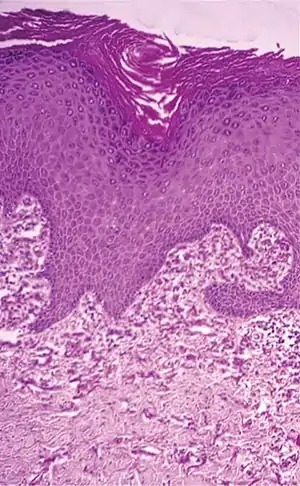

| Histopathology of perforating calcific elastosis: Clumping of short elastic fibers in the dermis.[2] | |